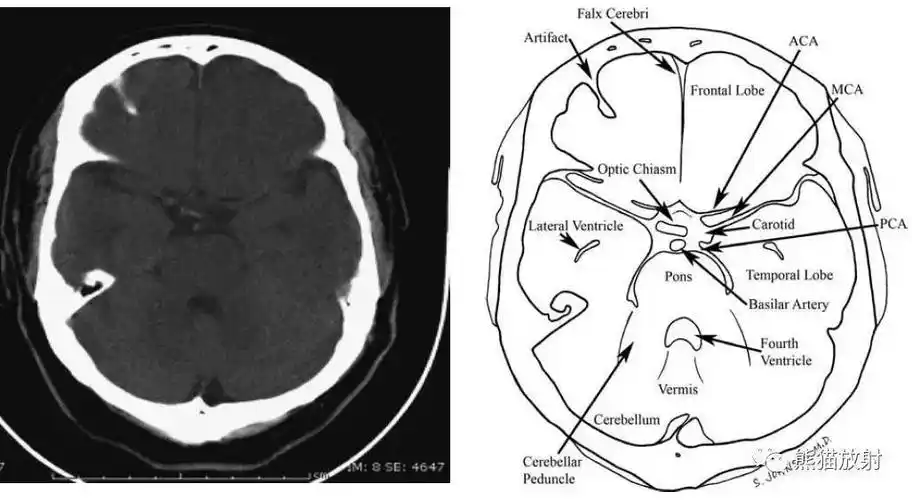

读懂头颅ct并不难教你成为读片小能手

超实用急诊头颅ct3b阅片法

影像总结头颅ct基本知识与常见病变

图-:2010年9月7日头颅ct整合.png